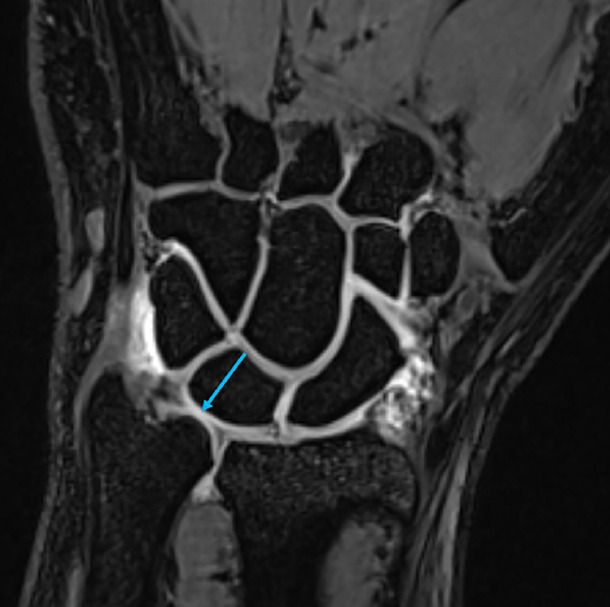

放射照相术是一个与技术密不可分的医学领域。在超声(US)、计算机断层扫描(CT)和磁共振成像(MRI)中获取图像对技术的依赖性非常高。虽然降低辐射剂量并不适用于US和MRI,但技术的进步使其在CT中成为可能,正在进行的研究旨在进一步优化。通过每种模式的进步所获得的图像的分辨率和诊断质量正在稳步提高。此外,技术进步大大缩短了CT和MRI的采集时间。人工智能(AI)的使用在世界范围内变得越来越普遍,也被纳入放射照相。该技术可以在超声检查中产生更准确和可重复的结果。机器学习为提高图像质量、创建更清晰、更有用的图像、甚至开发新的美国成像模式提供了巨大的潜力。此外,人工智能技术在CT和MRI中越来越普遍,用于图像评估、图像生成和增强图像质量。

Radiography is a field of medicine inherently intertwined with technology. The dependency on technology is very high for obtaining images in ultrasound (US), computed tomography (CT), and magnetic resonance imaging (MRI). Although the reduction in radiation dose is not applicable in US and MRI, advancements in technology have made it possible in CT, with ongoing studies aimed at further optimization. The resolution and diagnostic quality of images obtained through advancements in each modality are steadily improving. Additionally, technological progress has significantly shortened acquisition times for CT and MRI. The use of artificial intelligence (AI), which is becoming increasingly widespread worldwide, has also been incorporated into radiography. This technology can produce more accurate and reproducible results in US examinations. Machine learning offers great potential for improving image quality, creating more distinct and useful images, and even developing new US imaging modalities. Furthermore, AI technologies are increasingly prevalent in CT and MRI for image evaluation, image generation, and enhanced image quality.